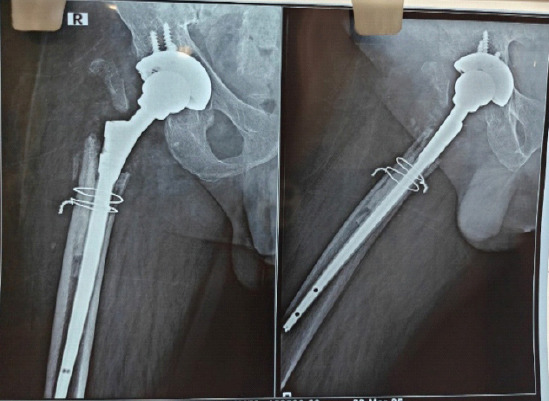

Case report: We report the case of a 52-year-old male with rheumatoid arthritis on immunosuppressive therapy, who presented with acute right hip pain, swelling, and purulent wound discharge 3 months after revision total hip arthroplasty. Initial workup revealed elevated inflammatory markers and signs of joint infection (JI). Conventional microbiological methods including Gram stain, acid-fast bacilli testing, and enrichment cultures were inconclusive. However, syndromic multiplex polymerase chain reaction (PCR) using the BioFire® JI panel detected H. influenzae within 2 h of intraoperative sample collection. The patient underwent debridement, targeted antibiotic therapy, and implant retention (DAIR). Empirical therapy with meropenem and vancomycin was promptly de-escalated to intravenous ceftriaxone, based on PCR results. Clinical recovery was marked by rapid decline in C-reactive protein, resolution of symptoms, and a successful switch to oral therapy. At 6-week and 16-week follow-up, the patient was asymptomatic, with normal inflammatory markers and radiographs, and a functioning retained implant.